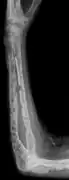

The diagnostic examination of a person with suspected multiple myeloma typically includes a skeletal survey. This is a series of X-rays of the skull, axial skeleton, and proximal long bones. Myeloma activity sometimes appears as "lytic lesions" (with local disappearance of normal bone due to resorption) or as "punched-out lesions" on the skull X-ray ("raindrop skull"). Lesions may also be sclerotic, which is seen as radiodense.[76] Overall, the radiodensity of myeloma is between −30 and 120 Hounsfield units (HU).[77] Magnetic resonance imaging is more sensitive than simple X-rays in the detection of lytic lesions, and may supersede a skeletal survey, especially when vertebral disease is suspected. Occasionally, a CT scan is performed to measure the size of soft-tissue plasmacytomas. Nuclear Medicine Bone scans are typically not of any additional value in the workup of people with myeloma (no new bone formation; lytic lesions not well visualized on nuclear bone scan).

X-ray of the forearm, with lytic lesions